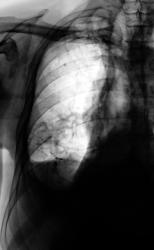

Левосторонний экссудативный плеврит.

До и после пункции.